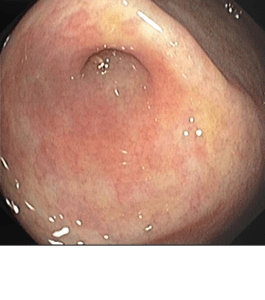

La polipectomía es un procedimiento endoscópico que se utiliza para extraer pólipos en diversas partes del tracto gastrointestinal, como el esófago, estómago, duodeno o colon. Esta técnica quirúrgica mínimamente invasiva no requiere incisiones y se realiza bajo sedación para la comodidad del paciente.

Durante la polipectomía, un endoscopio flexible equipado con una pequeña herramienta en forma de asa se introduce a través de la boca o el recto, según la ubicación del pólipo. Una vez que se localiza el pólipo, se utiliza el asa para capturar y cortar el pólipo de la pared del órgano. Es común cauterizar la base del pólipo con energía eléctrica o calor para prevenir la recurrencia (recidiva). Este paso ayuda a sellar los vasos sanguíneos y reduce el riesgo de sangrado.

La polipectomía es esencial para la detección temprana y la prevención del cáncer colorrectal, ya que muchos cánceres de colon se desarrollan a partir de pólipos adenomatosos. Al remover estos pólipos, se reducen significativamente las posibilidades de que se conviertan en cáncer en el futuro. Además, el examen histológico de los pólipos removidos proporciona información crucial sobre el riesgo de cáncer y guía el manejo clínico posterior.